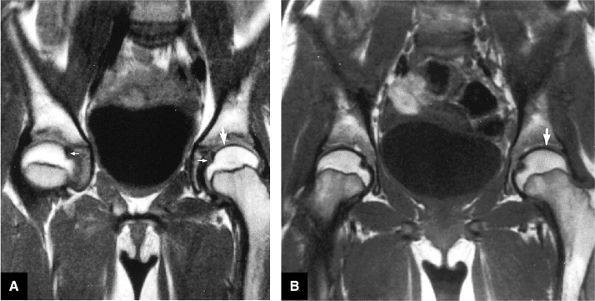

FIGURE 3.49 ● A normal cortical articular ridge of the acetabulum (arrow) is seen on (A) T2*-weighted coronal and (B) 3D CT images. This bony ridge should not be mistaken for osseous pathology. The acetabular notch (open arrow) is shown on the 3D CT rendering. (A: TR, 400 msec; TE, 20 msec; flip angle, 25°). (C) Arthroscopic view of acetabular notch.